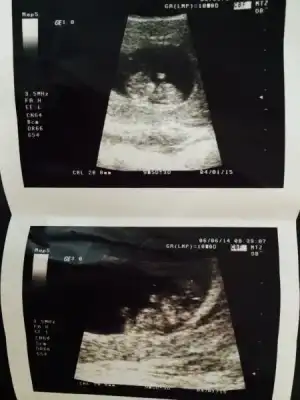

:34: bizim seninle aramızda 1 gün var. iki gün önceki ultrason görüntüsünü koydum. hala bişey diyen olmadı. ama benimkinde de çıkıntı net değil. bende tam anlayamadım. kız mı dedim kendi kendime. ama 1 oğlum var bu da kız olsun isterim yani, o yüzden mi kıza yoruyorum bilmiyorum. ama erkek nubu popoya paralel değil dik se eğer kız olma ihtimali daha yüksek bence. paralel net anlaşılmayabilir ama erkek anlaşılır bence, bu nub yöntemi aksi çıkan varmı bilmiyorumki

bak bu 2 gün önceki görüntü

pattosa bu usg sanırım 10 haftalık. . çok küçük çünkü henüz belli oaz bu haftada 11 hatta 12 hafta sonrası daha uygun..